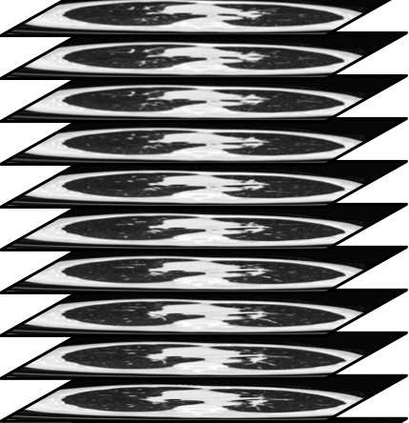

In clinical practice, anisotropic volumetric medical images with low through-plane resolution are commonly used due to short acquisition time and lower storage cost. Nevertheless, the coarse resolution may lead to difficulties in medical diagnosis by either physicians or computer-aided diagnosis algorithms. Deep learning-based volumetric super-resolution (SR) methods are feasible ways to improve resolution, with convolutional neural networks (CNN) at their core. Despite recent progress, these methods are limited by inherent properties of convolution operators, which ignore content relevance and cannot effectively model long-range dependencies. In addition, most of the existing methods use pseudo-paired volumes for training and evaluation, where pseudo low-resolution (LR) volumes are generated by a simple degradation of their high-resolution (HR) counterparts. However, the domain gap between pseudo- and real-LR volumes leads to the poor performance of these methods in practice. In this paper, we build the first public real-paired dataset RPLHR-CT as a benchmark for volumetric SR, and provide baseline results by re-implementing four state-of-the-art CNN-based methods. Considering the inherent shortcoming of CNN, we also propose a transformer volumetric super-resolution network (TVSRN) based on attention mechanisms, dispensing with convolutions entirely. This is the first research to use a pure transformer for CT volumetric SR. The experimental results show that TVSRN significantly outperforms all baselines on both PSNR and SSIM. Moreover, the TVSRN method achieves a better trade-off between the image quality, the number of parameters, and the running time. Data and code are available at https://github.com/smilenaxx/RPLHR-CT.